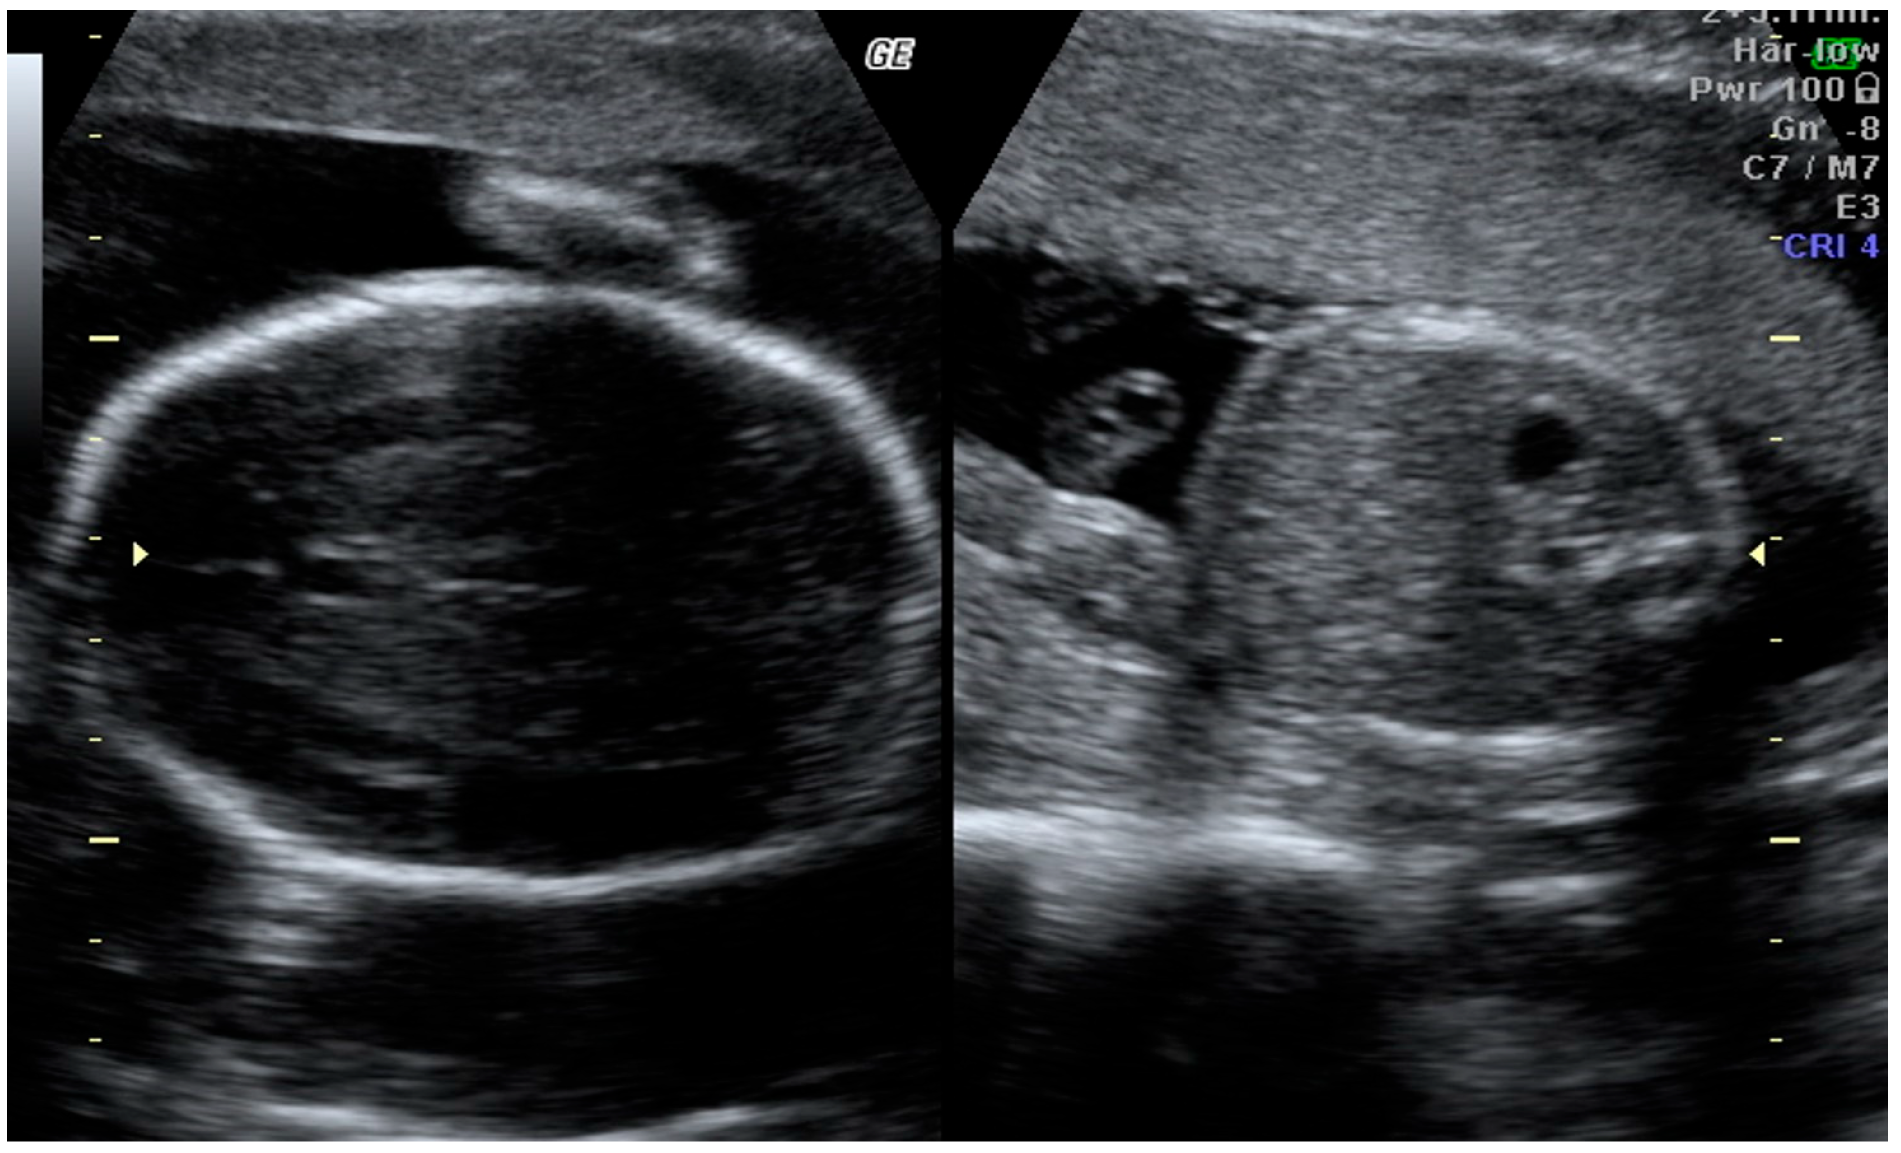

2.1. First-Trimester Findings

- PAPP-A: 0.7 MoM

- Beta-hCG: 0.73 MoM

- Nuchal Translucency (NT): 0.98 mm